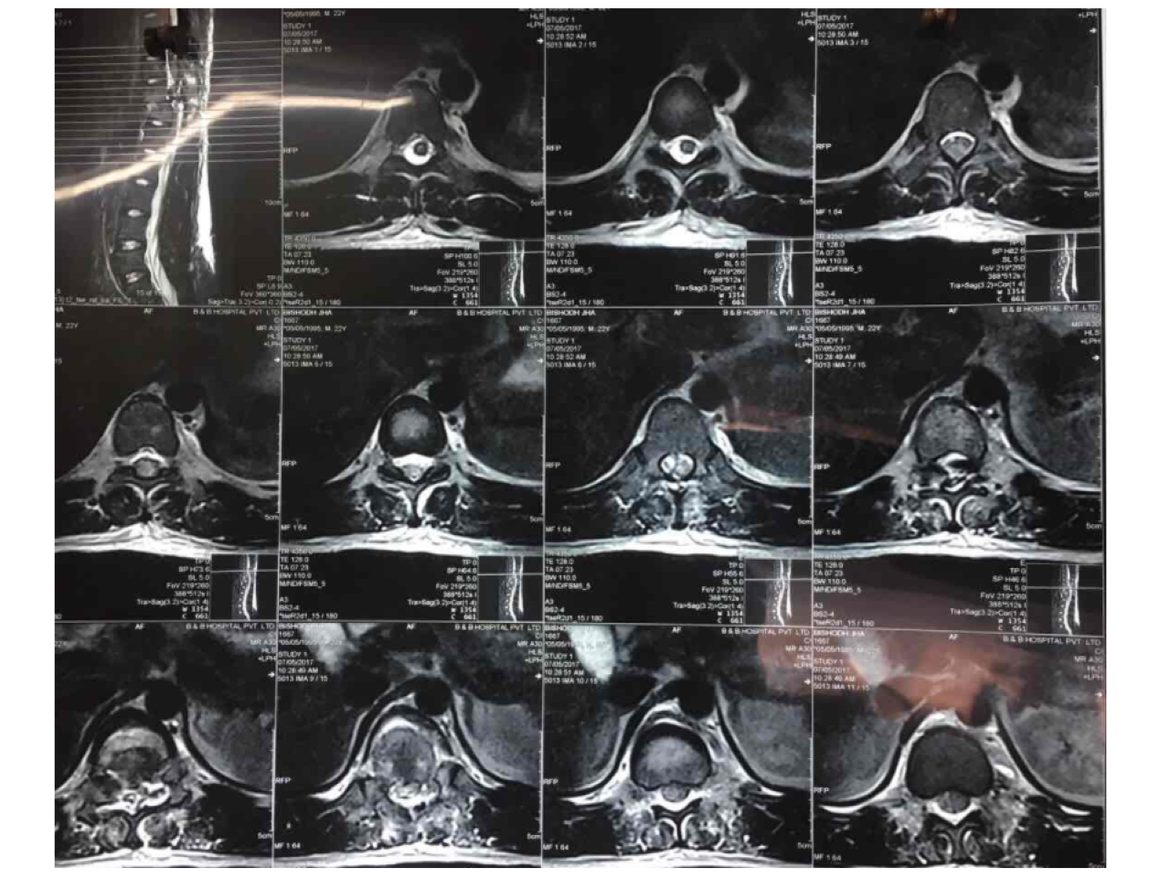

had an accident which broke my spinal cord, i was diagnosed with

paraplegia which means i have a complete spinal cord injury at t11 t12

level. My t12 vertebra was completely crushed & t11 was dislocated.